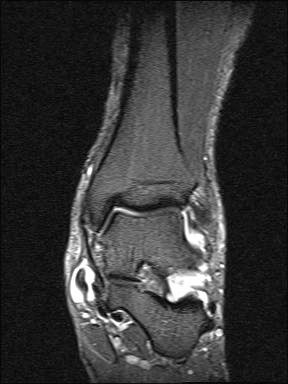

Aufgrund der geringen Zuverlässigkeit der klinischen Untersuchung und der konventionell radiologischen Bildgebung ist die Bildgebung der Wahl die Kernspintomographie (Szeimies 2014). Allerdings bestehen auch bei der Kernspintomographie klare Grenzen, vor allem hinsichtlich der Beurteilung der mechanischen Stabilität. Zuverlässige Aussagen sind möglich zum Ausmaß der Verletzung, insbesondere welche Bandanteile betroffen sind, sowie zu Begleitverletzungen. Chun et al. 11 berichteten über eine Sensitivität von 84% und eine Spezifität von 93,5% für Läsionen des Deltabandes im MRT. Befunde im MRT umfassen eine flächige Ödematisierung und Einblutung entlang des Deltabandes, meist unter Aussparung der kräftigen Pars tibiotalare posterior. Ein gewellter Verlauf, sowie eine Unterbrechung der Kontinuität der Faszikel sind Zeichen eines strukturellen Schadens. Teilweise finden sich Knochenkontussionsödeme, aber auch kortikale Absprengungen am lateralen Talusrand, der Talusschulter und am Außenknöchel. Fast immer findet sich ein Gelenkerguss (Abbildung 4).